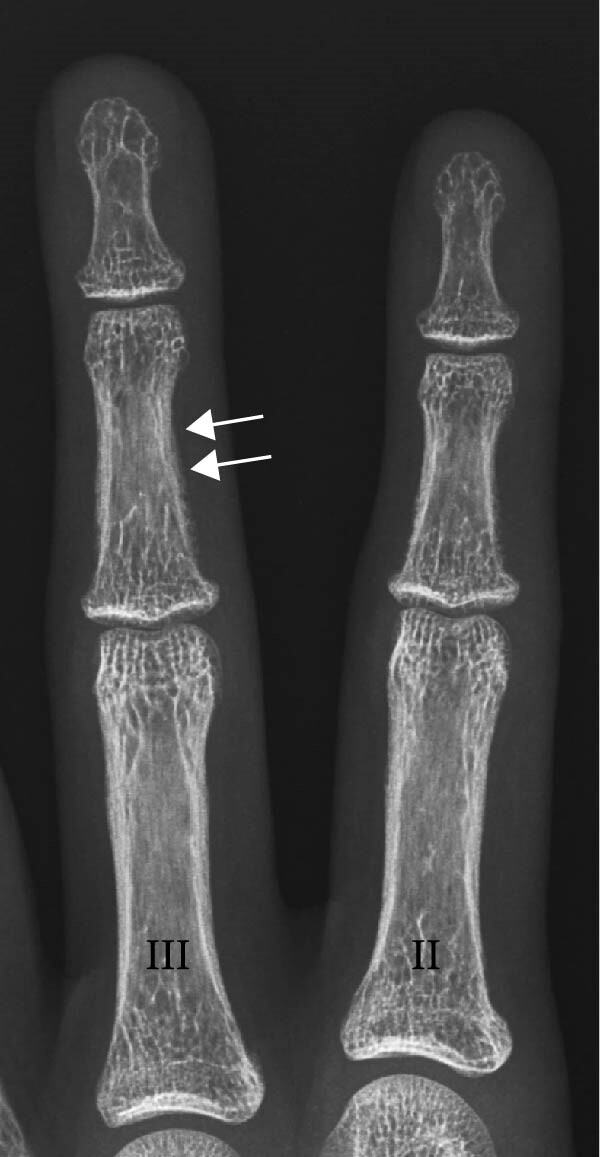

При дальнейшем обследовании у нее были обнаружены изменения костной ткани вследствие гиперпаратиреоза (рис. 3-4) и нефрокальциноз почек (по данным УЗИ).

Рисунок 3. Часть рентгенограммы кисти в переднезадней проекции (II – указательный палец, III – безымянный палец), где заметны снижение плотности костной ткани, кружевной вид кортикального слоя, субпериостальная резорбция костной ткани (стрелки).